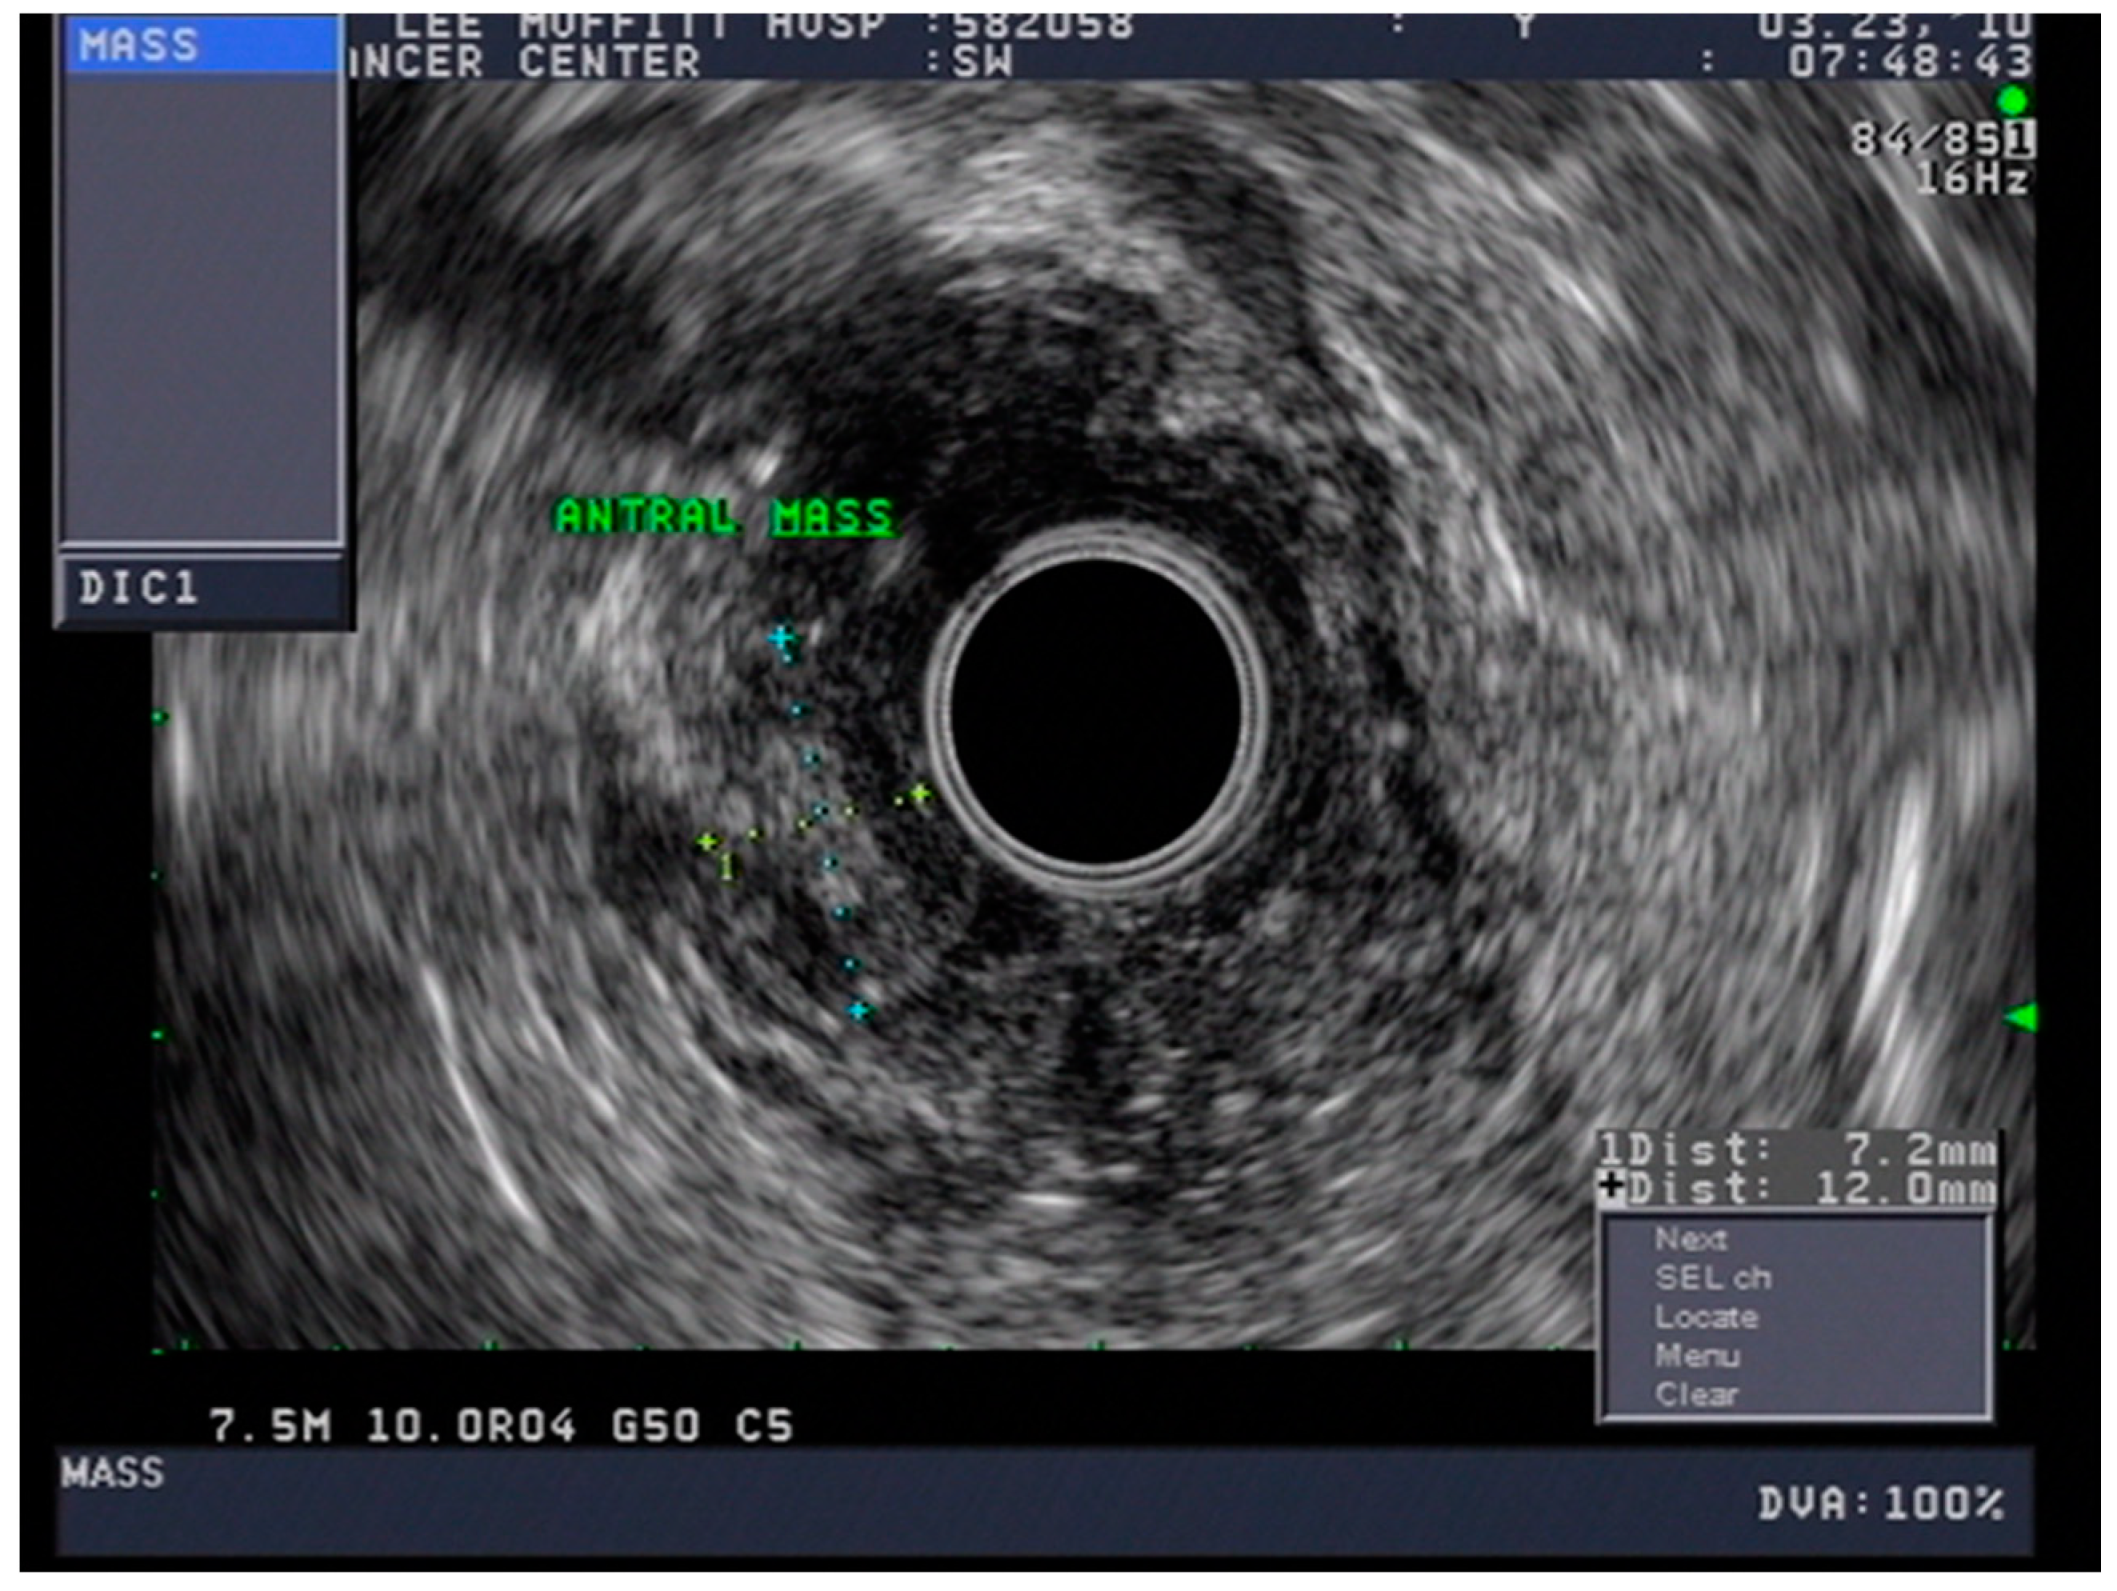

4.3. Endoscopic Ultrasound in Staging of Gastric Cancer

4.7. Staging

- Spolverato, G.; Ejaz, A.; Kim, Y.; Squires, M.H.; Poultsides, G.A.; Fields, R.C.; Schmidt, C.; Weber, S.M.; Votanopoulos, K.; Maithel, S.K.; et al. Use of Endoscopic Ultrasound in the Preoperative Staging of Gastric Cancer: A Multi-Institutional Study of the US Gastric Cancer Collaborative. J. Am. Coll. Surg. 2015, 220, 48–56. [Google Scholar] [CrossRef] [PubMed]

- Mocellin, S.; Pasquali, S. Diagnostic accuracy of endoscopic ultrasonography (EUS) for the preoperative locoregional staging of primary gastric cancer. Cochrane Database Syst. Rev. 2015, 2015, CD009944. [Google Scholar] [CrossRef]